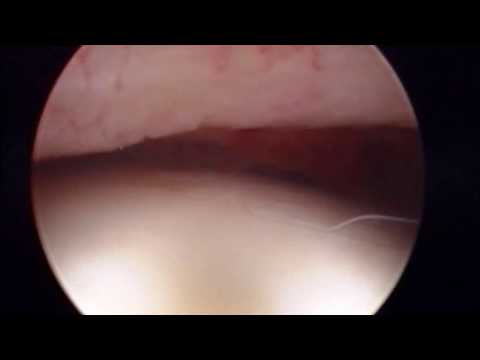

La Artroscopia es la cirugía en que se introduce una cámara en el interior de la articulación, permitiendo ver y tratar estructuras que el ojo humano difícilmente podría apreciar.